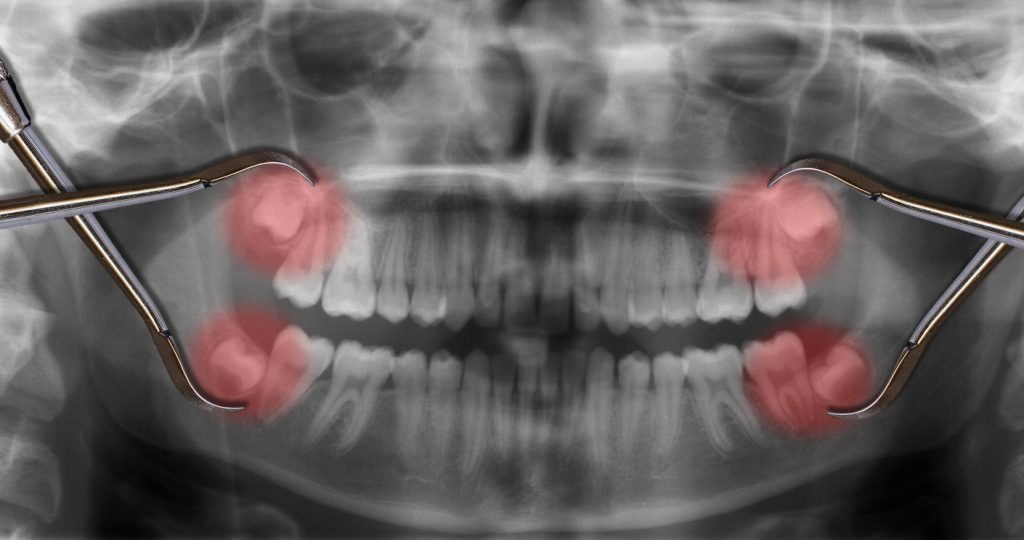

Read moreDetailsضرس العقل أو Wisdom Teeth هو الضرس الثالث والأخير من حيث الظهور بآخر الفم، وعادةً ما يظهر في السنوات القليلة...